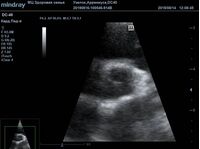

Найти их очень просто, достаточно сечений LAXLV (длинная ось) и SAXBASE (короткая ось). Специфические крупные шаровидные структуры – узелки Аррениуса - на кончиках полулуний клапана обнаружил ультразвуковой прибор Mindray DC-40. В цветовом допплере без труда определяется аортальная регургитация легкой степени. Оценить её можно в CFM по соотношению JW/LVOT.

Приборы среднего класса прекрасно справляются с этой задачей. Чтобы использовать возможности прибора на максимум необходимо уменьшить поле обзора (Front of view - FOV), тогда увеличится частота кадров и качество картинки при поиске мелких структур. Также частота кадров увеличивается при снижении уровня persistence, что актуально для детского возраста и высокой частоты сокращения сердца.